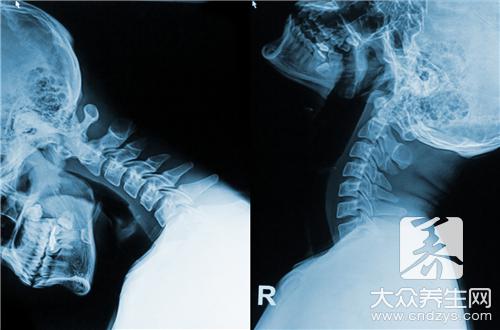

现在人多少都会有颈椎病,而且有的人颈椎病的症状很严重甚至出现了瘫痪的现象,因此我们平时都要注重颈椎病的日常保健,这样才能够更好的缓解和控制病情,我们平时可以多学习颈椎病的自我按摩疗法,经常按摩,热敷,也可以用食疗方法治疗颈椎病,另外还要保持好的心情。